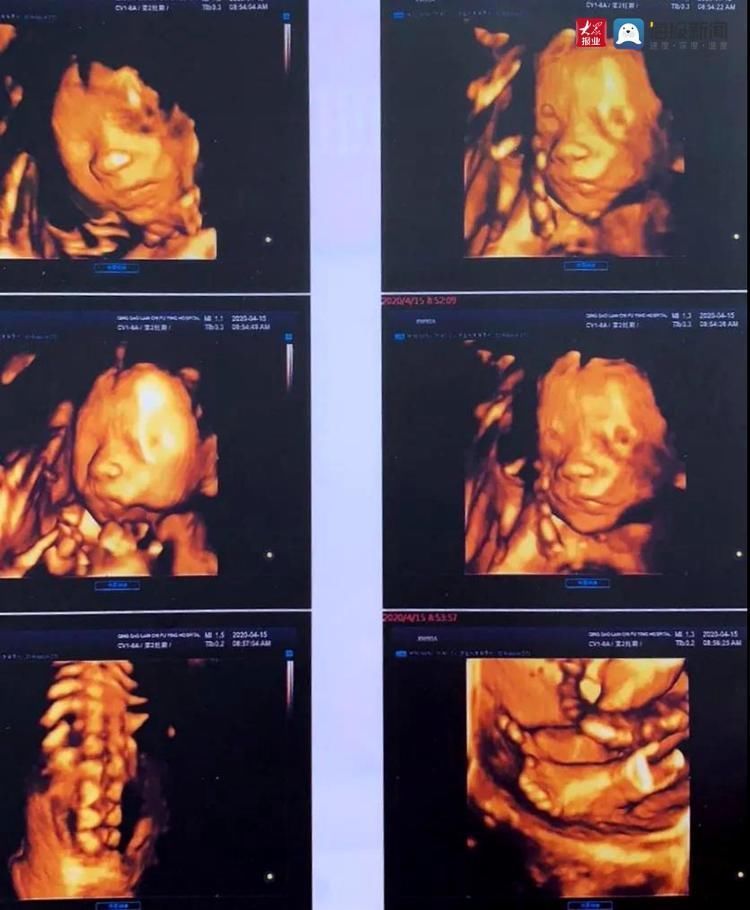

第一次接触莲池是做5D彩超。2020年4月15号,我按照预约的时间早早来到莲池,帮忙预约的郭主任带我们去一楼挂了包院长的号,介绍了医院的情况,还亲自送到二楼产科门诊才离开。

见到包院,感觉好亲切啊,说话很温柔,讲解的也细致;做5D的小姐姐也超级温柔的,会给你讲“看,这是宝宝的小脚,这是宝宝的小手,5个小指头,宝宝很活泼,哎呀,又跑了。”第一次看到宝宝的样子,感觉很神奇,一个小生命在孕育。